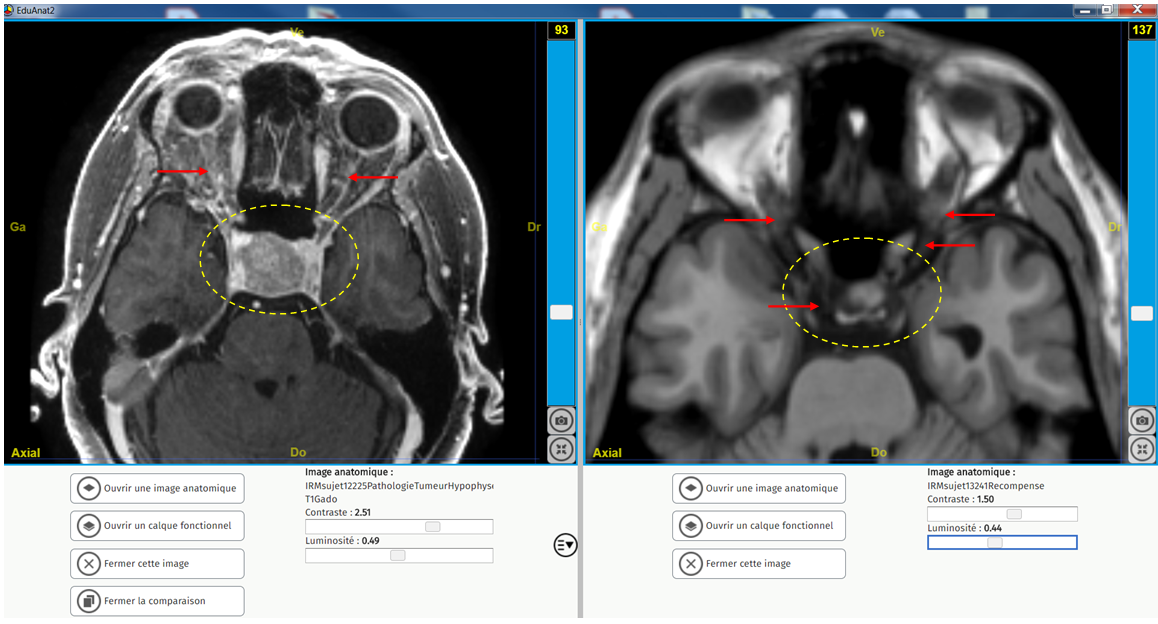

Tumeur Hypophyse vision légendé